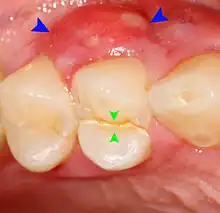

A periodontal abscess (lateral abscess) is a collection of pus that forms in the gingival crevices, usually as a result of chronic periodontitis where the pockets are pathologically deepened greater than 3mm. A healthy gingival pocket will contain bacteria and some calculus kept in check by the immune system. As the pocket deepens, the balance is disrupted, and an acute inflammatory response results, forming pus. The debris and swelling then disrupt the normal flow of fluids into and out of the pocket, rapidly accelerating the inflammatory cycle. Larger pockets also have a greater likelihood of collecting food debris, creating additional sources of infection.[24]: 443

Periodontal abscesses are less common than apical abscesses, but are still frequent. The key difference between the two is that the pulp of the tooth tends to be alive, and will respond normally to pulp tests. However, an untreated periodontal abscess may still cause the pulp to die if it reaches the tooth apex in a periodontic-endodontic lesion. A periodontal abscess can occur as the result of tooth fracture, food packing into a periodontal pocket (with poorly shaped fillings), calculus build-up, and lowered immune responses (such as in diabetes). Periodontal abscess can also occur after periodontal scaling, which causes the gums to tighten around the teeth and trap debris in the pocket.[24]: 444–445 Toothache caused by a periodontal abscess is generally deep and throbbing. The oral mucosa covering an early periodontal abscess appears erythematous (red), swollen, shiny, and painful to touch.[25]

A variant of the periodontal abscess is the gingival abscess, which is limited to the gingival margin, has a quicker onset, and is typically caused by trauma from items such as a fishbone, toothpick, or toothbrush, rather than chronic periodontitis.[24]: 446–447 The treatment of a periodontal abscess is similar to the management of dental abscesses in general (see: Treatment). However, since the tooth is typically alive, there is no difficulty in accessing the source of infection and, therefore, antibiotics are more routinely used in conjunction with scaling and root planing.[26] The occurrence of a periodontal abscess usually indicates advanced periodontal disease, which requires correct management to prevent recurrent abscesses, including daily cleaning below the gumline to prevent the buildup of subgingival plaque and calculus.